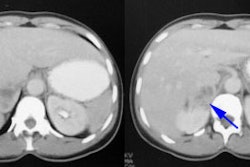

Dilated non-obstructed right collecting system: The right collecting system demonstrates prompt washout of tracer with a T1/2 of 6.2 minutes. The washout curve is somewhat convex in shape, but there is only about 11.5% retained collecting system activity and the findings were most consistent with a dilated non-obstructed system. |